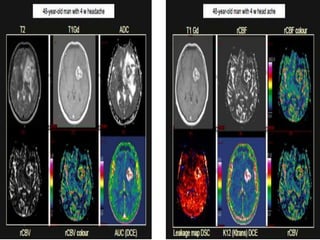

Forty-nine-year-old woman with a glioblastoma in the frontal lobes. The

region within the tumour with pronounced signal enhancement is marked

with circle on ASL CBF, DSC rCBF (colour-coded) and DSC rCBV (grey scale).